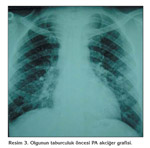

Olgu, su?i?e?i pn?monisi ve solunum yetmezli?i ?n tan?s? ile servisimize yat?r?ld?. Hastaya antiviral asiklovir 10 mg/kg sekiz saatte bir ve profilaktik ampisilin-sulbaktam tedavisi ba?land?. Tedaviden ?? saat sonras?nda ate?i d??t?. Fakat takipne, ta?ikardi devam etti. Konf?zyon geli?ti. AKG pH: 7.2, PaCO2: 47.5 mmHg, PaO2: 48.2 mmHg, HCO3: 20.8 mmol/L ve SaO2: %77.7 ?l??ld?. Oksijen deste?ine ra?men sat?rasyonlar? artmayan, solunum say?s? y?ksek seyreden, PaCO2 d?zeyleri artan, respiratuar asidoz ve konf?zyon geli?en olguya solunum yetmezli?i nedeniyle invaziv mekanik ventilasyon ba?land?. Klini?i 36 saat sonra d?zelen hasta ekst?be edildi ve bir hafta sonra taburcu edildi. Kontrol PAakci?er grafisi lezyonlarda belirgin d?zelme g?sterdi (Resim 3). Hastan?n varisella zoster vir?s (VZV) IgM?si pozitif saptand?.

VZV?nin neden oldu?u su?i?e?i ?ocukluk d?neminde ?o?unlukla hafif seyrederken, eri?kinlerde e?lik edebilen pn?moni nedeniyle ?l?me neden olabilmektedir. Su?i?e?i pn?monisi genellikle deri bulgular? ortaya ??kt?ktan sonra geli?mekle birlikte ?ncesinde de ortaya ??kabilmektedir. Akci?er grafisi yayg?n interstisyel veya nod?ler lezyonlar g?stermektedir (2,3,4,5). Olgumuzda pn?moni semptomlar? deri bulgular? sonras? alt?nc? g?nde ortaya ??km?? ve ayn? g?nde ?ekilen akci?er grafisi normal izlenmi?. Acile ba?vurdu?unda ate?, takipne, nefes darl??? ve t?m v?cutta yayg?n olarak deri bulgular? vard?. Hemoptizi belirgindi, konf?zyona meyil mevcuttu ve a??r hipoksiyle ili?kili oldu?u d???n?ld?. PA akci?er grafisinde yayg?n interstisyel ve nod?ler lezyonlar saptand?. Su?i?e?i pn?monisi tan?s? temas anamnezi, uygun klinik ve radyolojik bulgular varl???nda konulmaktad?r ve serolojik ?al??malar tan?y? desteklemektedir (6,7). Biz tan?m?z? temas anamnezi, klinik, radyolojik ve serolojik olarak koyduk.